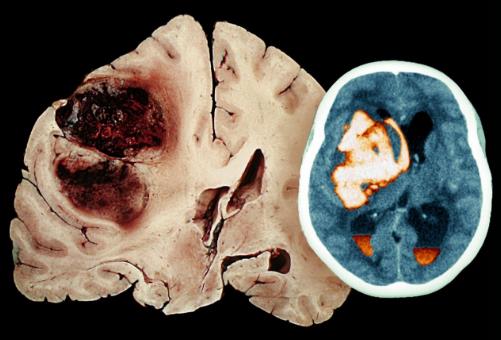

在了解腦出血的前兆之前我們先要看看什么是腦出血。腦溢血又稱腦出血、發病急且進展迅速。數據顯示在發生腦出血的患者中50%有先兆癥狀。腦溢血是指腦內微血管破裂出血是老年人的常見病好發于寒冷的冬季。常常表現為突然的一側肢體麻木、無力或癱瘓,因此病人會在毫無防備的情況下跌倒或手中的物品突然掉地同時伴有口角歪斜、流口水、語言含糊不清或失語,嚴重者伴有意識障礙、大小便失禁等。病因多與高血壓、動脈硬化有關具有起病急、后遺癥多等特點對老人的危害很大是中老年人致死性疾病之一。